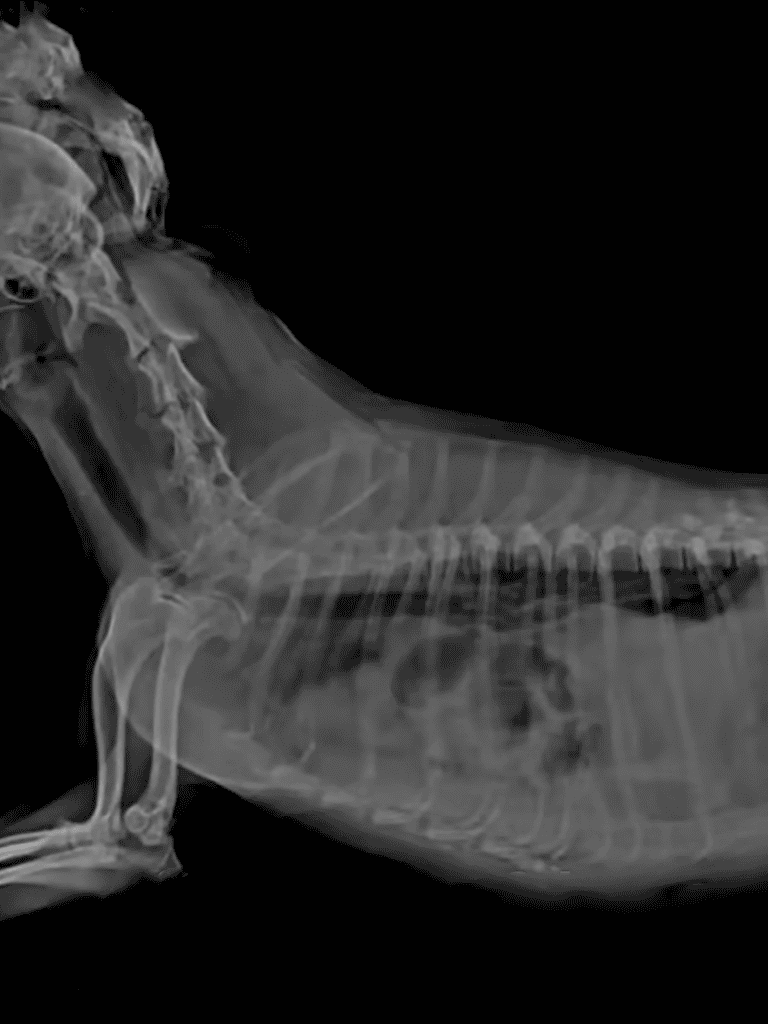

When we rushed her to the hospital, the news was shocking yet hopeful. An X-ray laid bare the truth we couldn’t see: nestled within her abdomen was a massive, 2.6 kg benign tumor, demanding immediate surgery.

In a well-orchestrated procedure, the surgeons deftly removed the tumor in just two hours. Her recovery journey had begun.